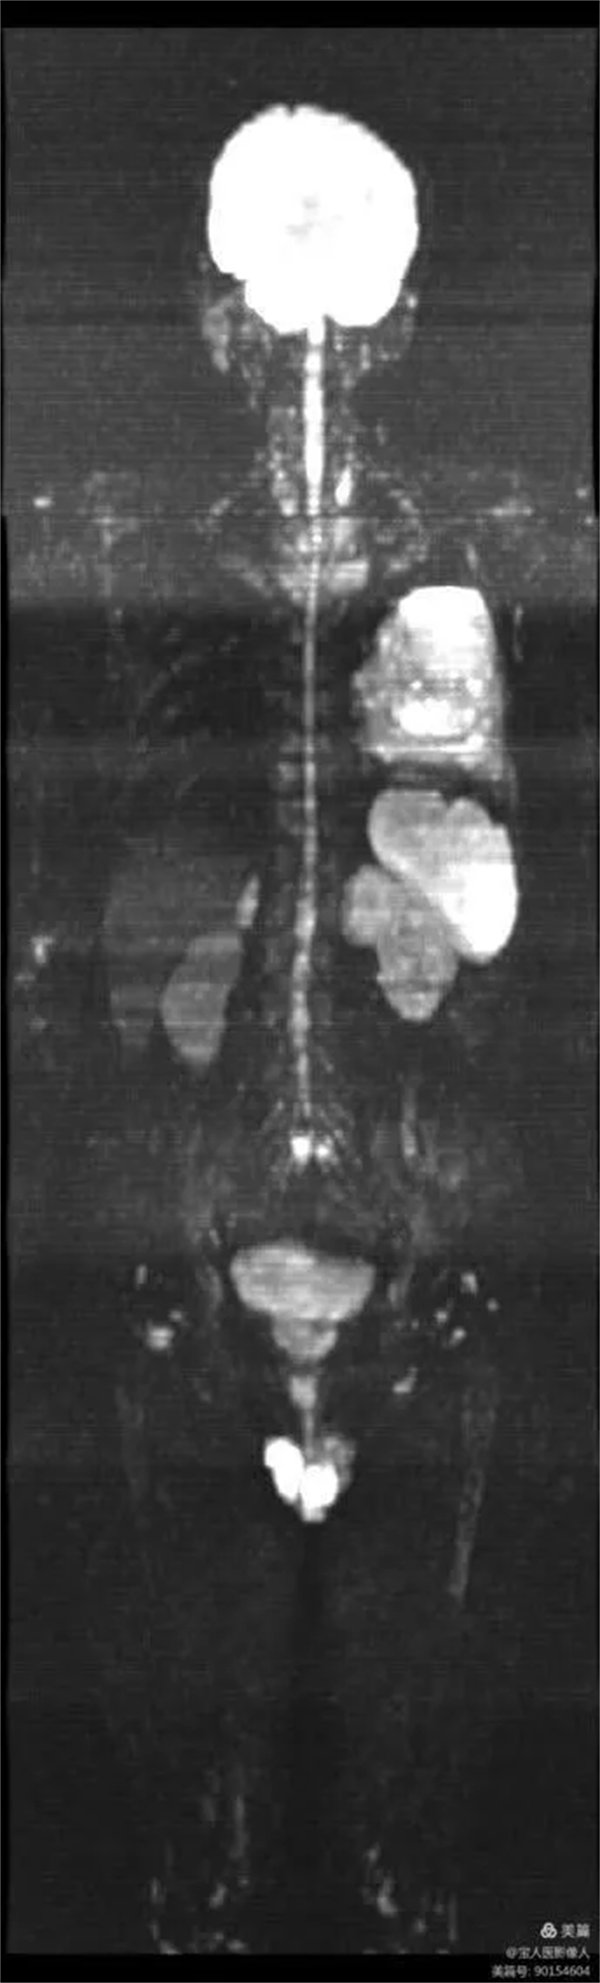

患者,男,左肺病變,為了查找全身有無其它病灶,明確分期,制定最合適的診療方案,臨床醫(yī)生決定行“類PET”即全身磁共振彌散成像(WB-DWI)檢查。

圖1:全身彌散成像圖像

磁共振全身彌散加權(quán)成像(WB-DWI),是將彌散加權(quán)成像技術(shù)與自動拼接技術(shù)和全景成像矩陣相結(jié)合而獲得全身的彌散加權(quán)成像影像。所得影像經(jīng)黑白翻轉(zhuǎn)后可達(dá)到與正電子發(fā)射計(jì)算機(jī)體層顯像(PET)影像類似的效果,故被稱為“類PET”,是近年來發(fā)展起來的全新影像檢查新技術(shù)。

該技術(shù)能夠進(jìn)行全身大范圍掃描,并加以3D后處理重建,可獲得全身腫瘤篩查、良惡性腫瘤的鑒別、腫瘤TNM分期及療效隨診等診斷信息,全身彌散技術(shù)把肌肉、脂肪、肝臟等組織背景信號抑制掉,突出了病變的顯示,大大提高了病變組織尤其是惡性腫瘤及其轉(zhuǎn)移灶的檢出率。